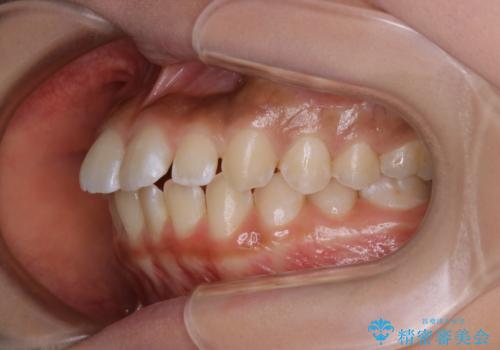

短期間ですきっ歯を改善:インビザラインLite

- 上の歯がすきっ歯なのと、歯が出ている気がするとご相談にいらした方です。

奥歯の噛み合わせに大きな問題がなく、患者様のご希望もあったため、前歯部メインで治療するインビザラインLiteで治療を行いました。

日常的に舌を突出する癖があったため、後戻り防止のために舌および口唇の筋機能訓練も合わせて行いました。

横顔のシルエットが改善し、口元もスッキリとなりました。

舌癖がある方は、歯を内側から押し出す力が日常的に働くため、矯正治療後も歯と歯の隙間が開いてしまうなどの後戻りのリスクが高いことが知られています。舌の正しいポジショニングやお口周りの筋肉のトレーニングを行うことで後戻りのリスクを減らすことが可能です。